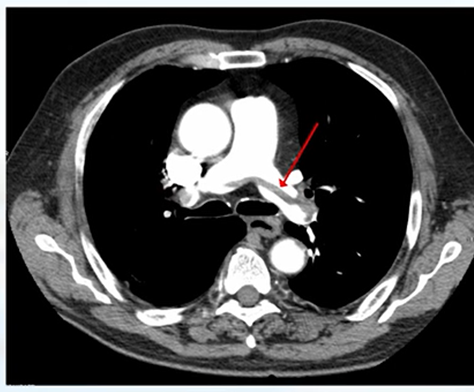

PEを疑ったら動脈相と静脈相をオーダーする。

急性血栓はひも状で血管壁と遊離していることもある(saddle pulmonary embolism)